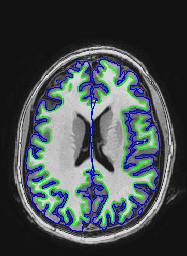

The following images show a T1 image with outlines for the outer boundary of gray matter (blue line) and white matter (green line).